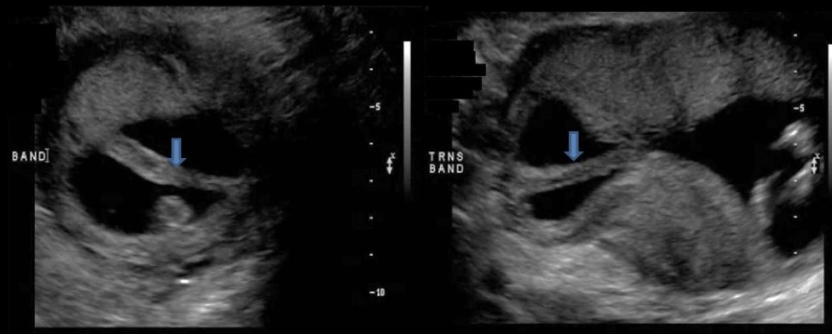

the cerebellum shows what sono sign

a) fruit salad

b) banana sign

c) lemon sign

d) string of pearls sign